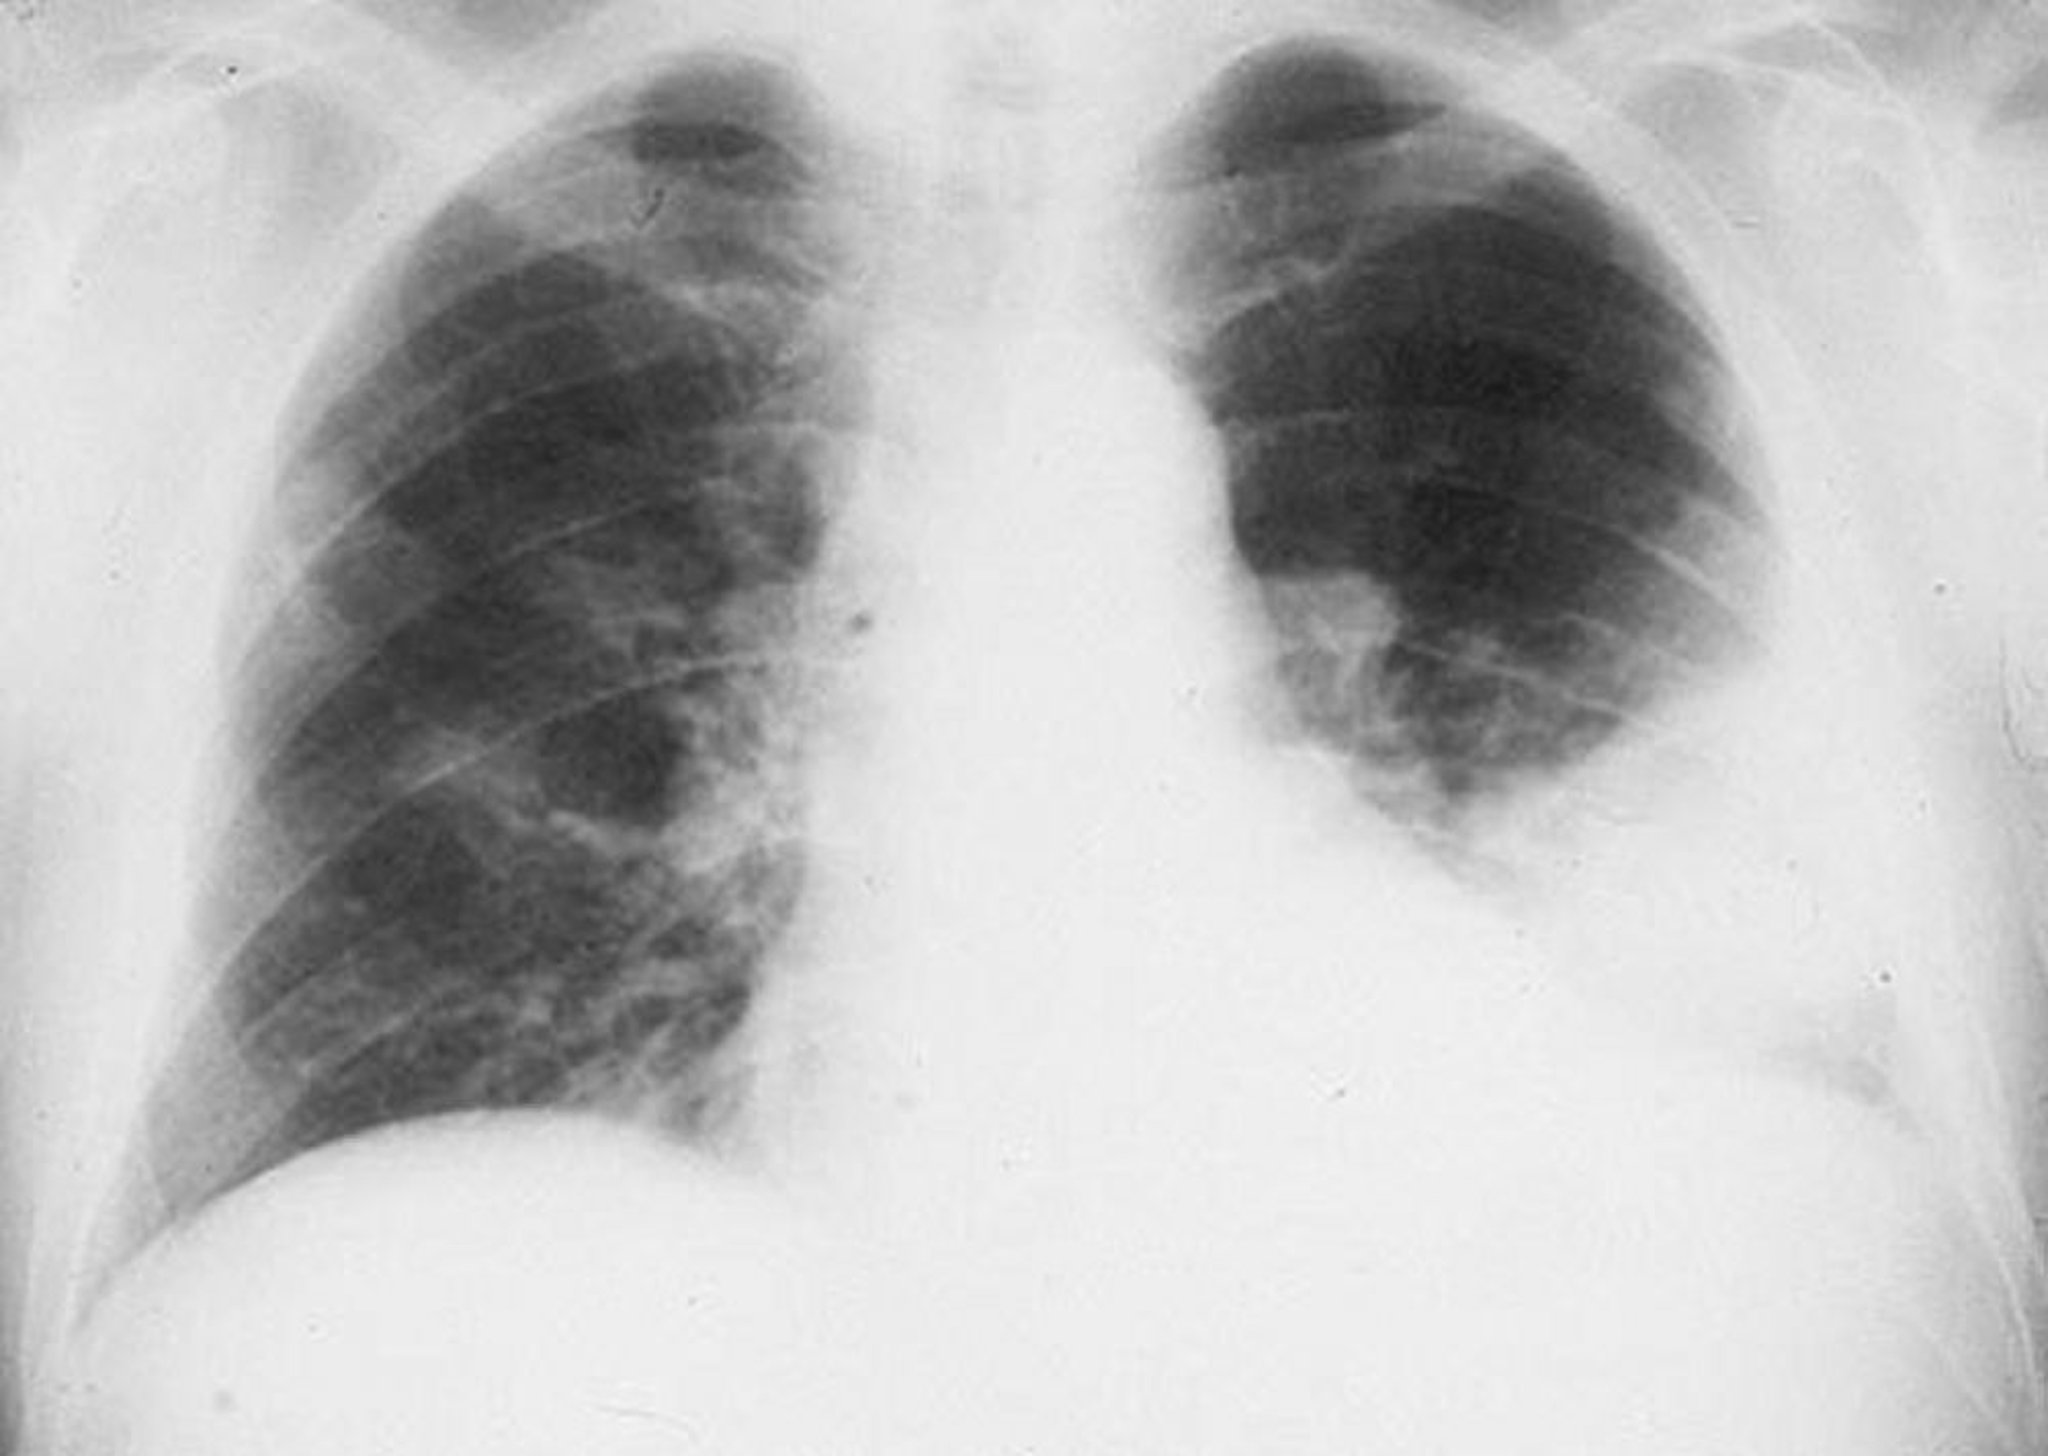

Left Lower Lobe Infiltrate

Alveolar infiltrate of the left lower lobe in a male with bacterial pneumonia.

By permission of the publisher. From Roberts R. In Atlas of Infectious Diseases: Pleuropulmonary and Bronchial Infections. Edited by GL Mandell (series editor) and MS Simberkoff. Philadelphia, Current Medicine, 1996.